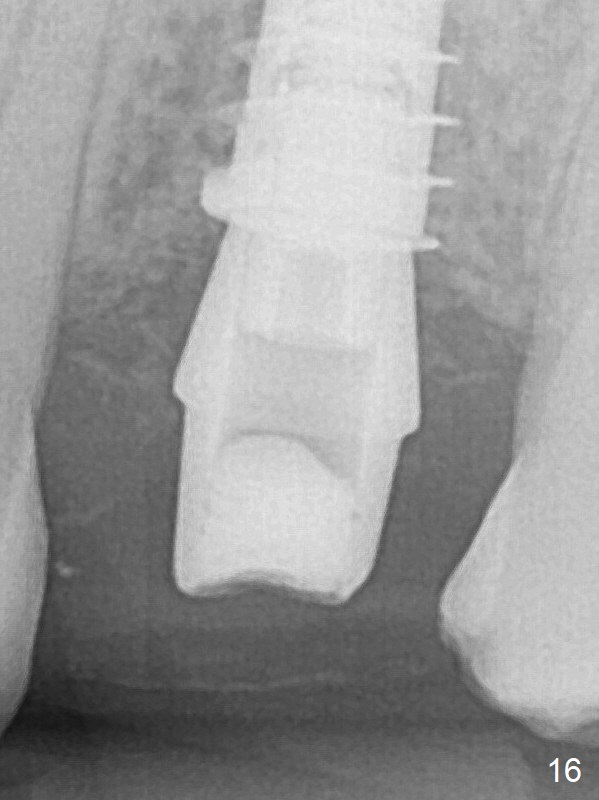

The buccal gingival inflammation subsides 1 week postop (Fig.13,14). There is no bone loss 4 months postop (Fig.15,16). The crown is recemented 6 months post cementation (probably due to short abutment); there is a residual cement (Fig.17 <), which is removed (Fig.18).